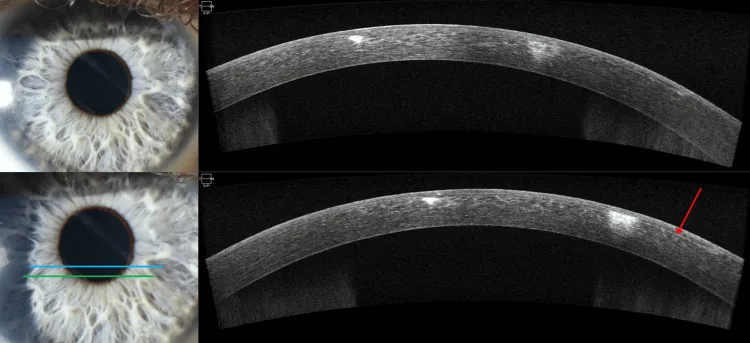

前眼部OCTによる評価:前眼部光干渉断層計(AS-OCT)により、角膜実質の混濁部位・範囲・深度を定量的に評価できる。治療効果の客観的判定にも有用である。